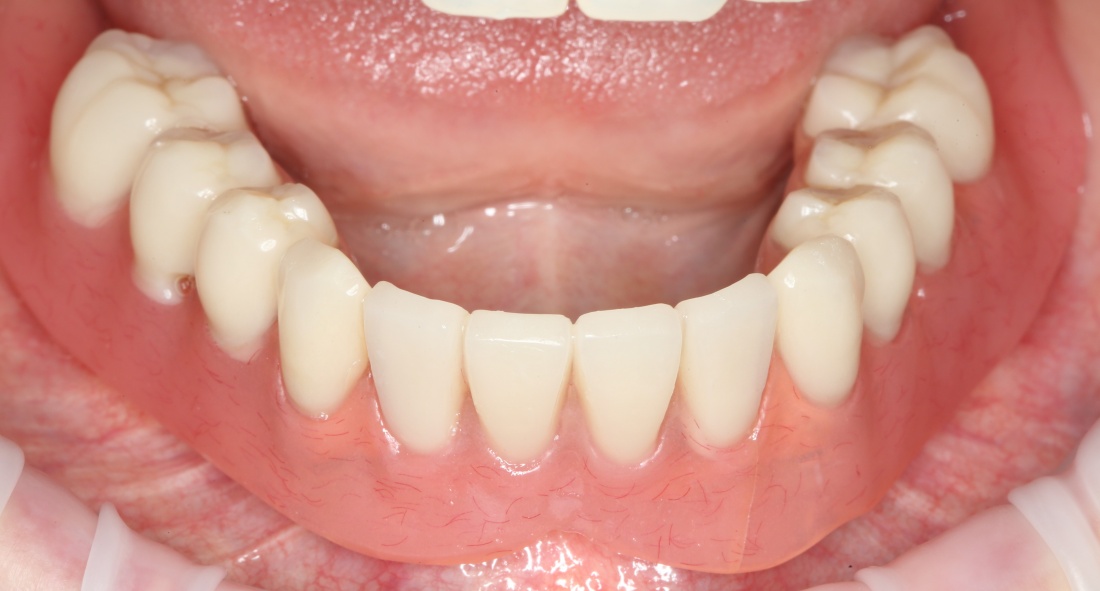

К счастью, уже через 6 недель после операции вдруг выяснилось, что ничего исправлять не нужно:

Фактически, нам осталось лишь дождаться приемлемого уровня остеоинтеграции имплантатов,  — примерно 2-3 месяца, — и можно переходить к постоянному протезированию.

Через три месяца мы сняли коронки с имплантатов, чтобы оценить качество формирования десневого контура:

С этого момента можно перестать переживать — десневой контур сформировался правильно, мы получили достаточный объём и качество окружающей платформу имплантата десны. Можно приступать к изготовлению постоянной протетики. Подрядчиком стала зуботехническая лаборатория French Creative, одна из топовых лабораторий Москвы.